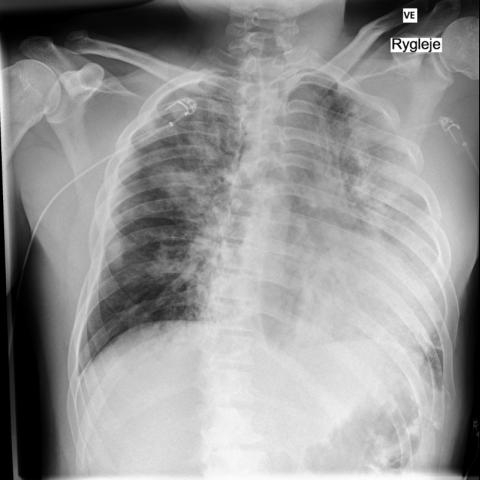

第 4 天复查,胸部 X 光显示肺部浸润明显减轻,与患者的临床恢复相对应。

a3f6c6ffd644b4c8867e8fd4e504a774.jpgb64d8400c5432c5926b5570a04335d02.jpg

经过 6 天的住院,患者恢复出院。

所有影像检查有效地记录了患者从严重肺窘迫到逐渐恢复的过程。